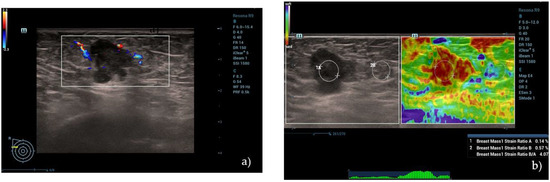

Figure 2.

(a) A hypoechoic lesion with irregular margins and vascular internal signs at color Doppler evaluation, classified as BI-RADS 5 by human operator. (b) Semi-quantitative elastography showing a value of strain ratio (4.07) suggestive of stiff lesion. (c) The same lesion, showing intermediate values at 2D SWE evaluation (21.95 kPa) and (d) high values at pSWE analysis (122.55 kPa). (e–h) “SmartBreast” assessment, suggestive of malignancy. At histological evaluation, it was a B5 lesion (infiltrating ductal carcinoma).

Subsequently, the lesion was evaluated using the 2D SWE technique. The investigator positioned the transducer so that it remained stable and perpendicular to the lesion without any pressure while maintaining only slight contact with the skin in order to minimize compression artifacts. The patient was instructed to maintain a short inspiratory apnea to avoid respiratory motion artifacts. A mechanical impulse from the probe generated shear waves in the breast tissue, and their propagation was analyzed in a real-time color map. In this technique, the impulse coming from the transducer generates a downward displacement of the tissue parallel to each grid, and the speed of propagation of the shear waves can be measured (m/s). Breast lesion stiffness was assessed by placing an ROI in the lesion and was expressed in kPa. The ROI was placed in the lesion so as to include as much tumoral area as possible, avoiding the loss of signal due to artifacts (Figure 2).

The pSWE assessment was based on the same physical principle of 2D SWE single-point stiffness was measured at different points of the lesion instead of an area. Each patient was asked to hold their breath, and the operator positioned the transducer perpendicular to the lesion without any pressure, waiting for the machine to take from 5 to 10 measurements at different points of the breast nodule in order to obtain a representation of the stiffness, expressed in Kpa, through maximum, minimum, and median values. The pSWE evaluation also included a quality bar that indicated the correct execution of the same (Figure 2d).